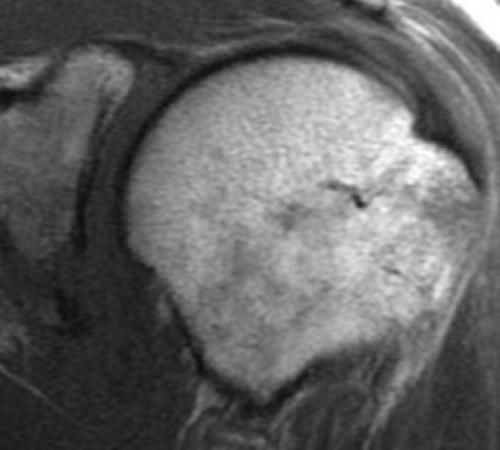

МРТ плечевого сустава. Корональные Т1-взвешенные МРТ. Переломы Хилла-Сакса и Банкарта.